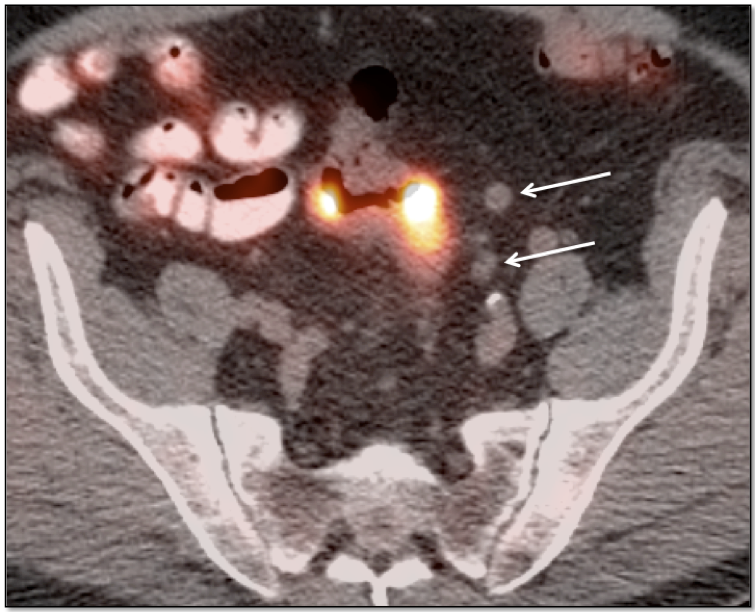

Metastases:

The most common sites of metastatic disease include the lymph nodes (regional & distant), liver, lung, peritoneal cavity, bones, brain and adrenal glands.

• Nodes under 8.0 mm may be non-avid only because they are beneath the resolution of PET (metastatic nodal assessment is discussed in detail, here).

• If < 8.0 mm, even mild uptake in a regional node is “highly suspicious”.

• If < 8.0 mm, even non-avid regional nodes are worrisome, and are considered “indeterminate”.